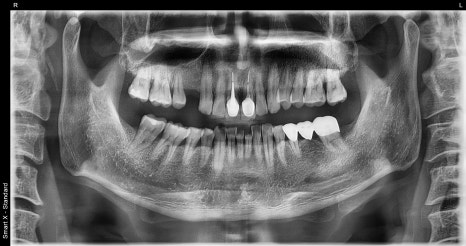

Left photo: Full-mouth X-ray (panoramic image) before treatment.

Right photo: Partial X-ray taken before root canal treatment after removing the existing crown (covered tooth).

➡ Deep decay had developed inside the old prosthesis, and root canal treatment was absolutely necessary.

➡ There was pain and discomfort, and along with root canal treatment, functional restoration was also performed with an implant in the missing front-tooth area.